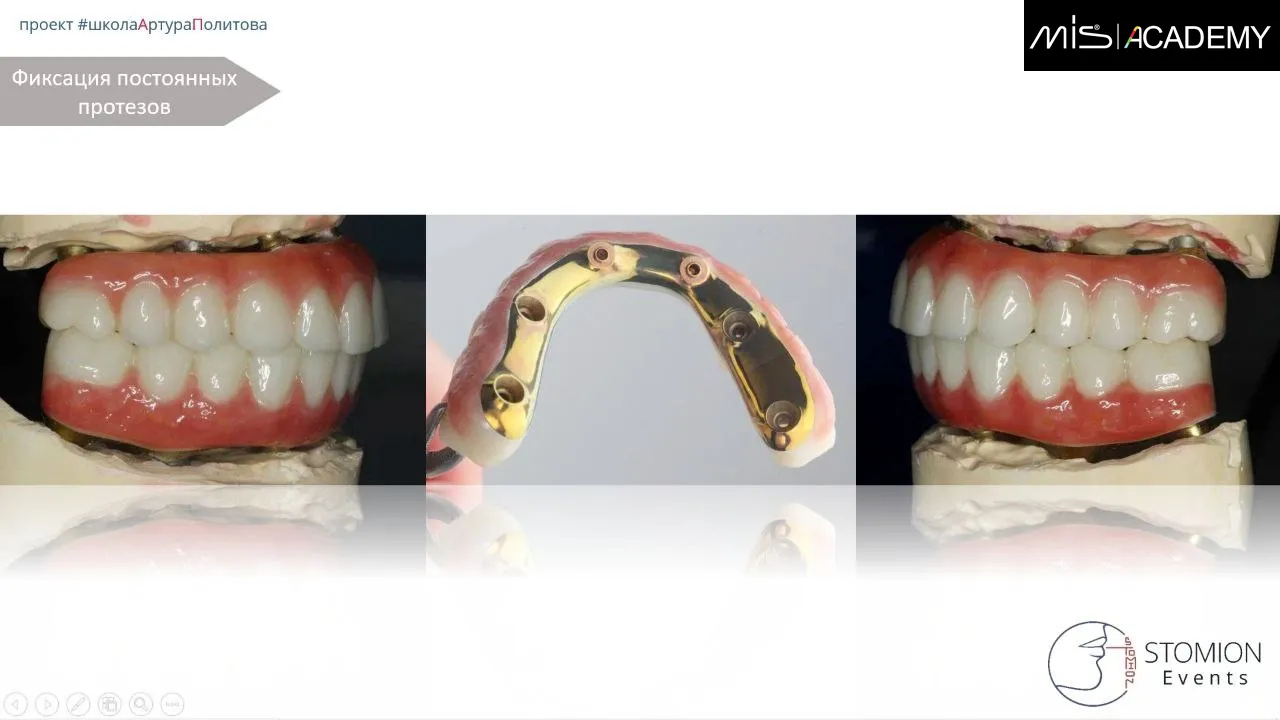

С 6-го месяца изготовление постоянной конструкции FP-3, диоксид циркония с нанесением, с фрезерованным, анодированным титановым каркасом с уровня мультиюнитов и коннектов.